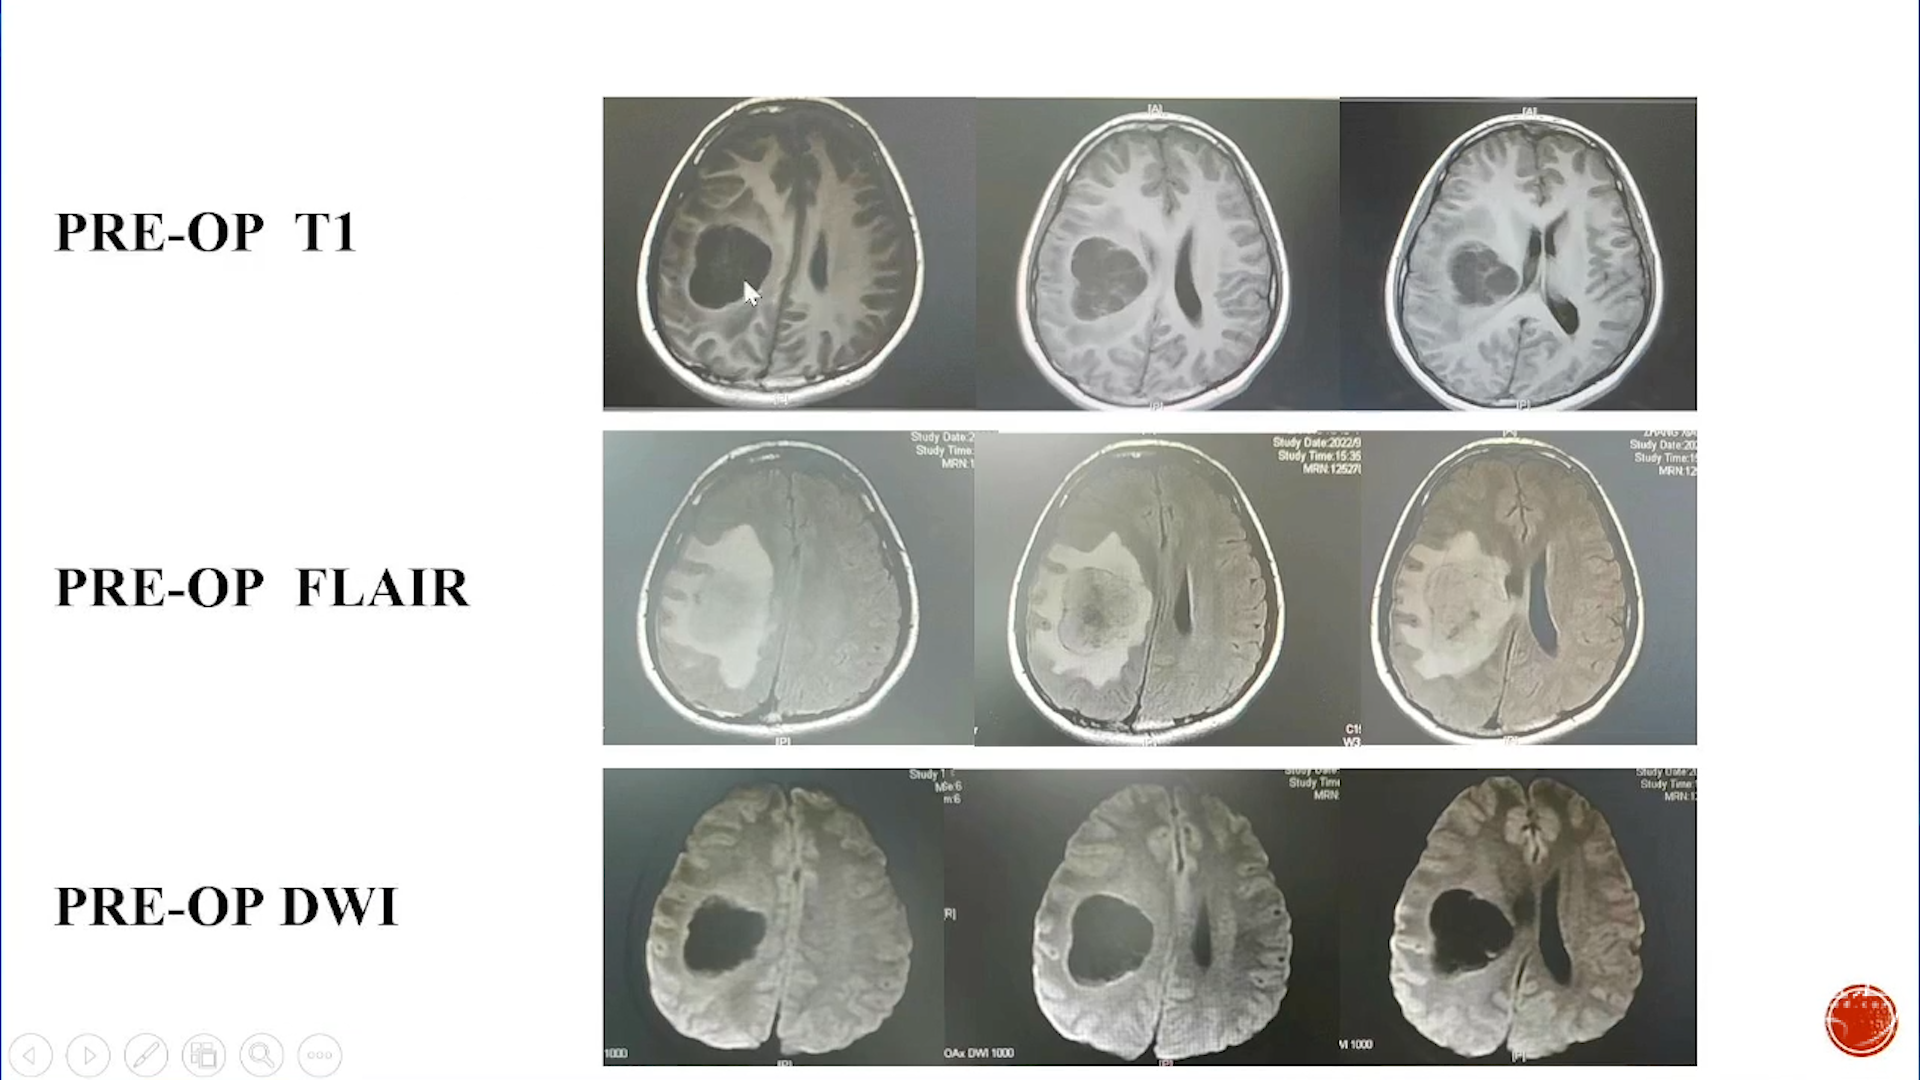

小脑星形细胞肿瘤

大脑半球儿童低级别胶质瘤

·致痫性肿瘤局限性肿瘤:节细胞胶质瘤、胚胎发育不良性神经上皮肿瘤(DNT)等

·弥漫性肿瘤